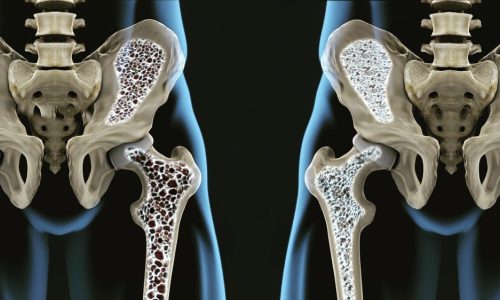

La densitometria MOC, ossia la Mineralometria Ossea Computerizzata, è un esame che serve a valutare lo stato di salute delle ossa, misurando la densità minerale ossea dello scheletro, dunque la massa e la quantità di minerali in esso presenti. Serve a determinare se la densità minerale si è ridotta e se è già comparsa l’osteoporosi, che comporta il rischio più o meno grave di fratture. Si rivela dunque utile soprattutto per le donne in menopausa e agli uomini over 60 con accertati fattori di rischio, poiché consente di identificare la malattia in fase precoce, una osteopenia, come campanello d’allarme, per il rischio più o meno grave di fratture.

Presso il Centro Medico Diagnostico OPTIMUM la Densitometria Ossea – MOC viene effettuata con un’apparecchiatura di ultimissima generazione: il sistema Horizon DXA è la più recente tecnologia di densitometria, che oltre a misurare la densità ossea permette una valutazione completa del rischio di frattura (FRAX™ – Valutazione Rischio di frattura a 10 anni).